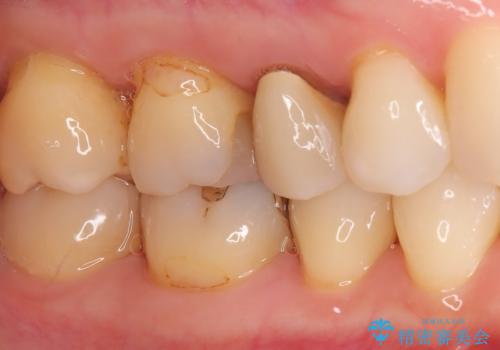

- 右上の奥歯(5番・6番)の被せ物の適合が悪く、歯ぐきが腫れやすい状態でした。患者さんご自身も「物がつまりやすい」「違和感がある」との訴えがあり、レントゲンと視診を行ったところ、被せ物の下にむし歯が進行していることが判明しました。特に右上5番は、神経の治療(根管治療)が過去に行われていましたが、根の先に炎症が残っており、治療のやり直しが必要と判断しました。

治療計画としては、まず古い被せ物を外し、虫歯の除去と右上5番の再根管治療を行った後、精密な形でセラミッククラウンを装着する方針としました。右上6番についても虫歯を除去し、必要な支台処置を行ったうえで同様にセラミッククラウンによる補綴を提案しました。

まずは両歯の古い被せ物を慎重に除去し、中のむし歯を確認しました。右上5番は神経の治療のやり直し(再根管治療)を行い、細菌感染を取り除いたうえで、根の中を密に封鎖しました。治療中は仮歯を入れて審美性と機能性を保ちつつ、歯ぐきの状態も改善していきました。